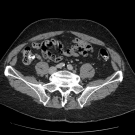

Carly Gunderson; Carey Roberts, DO; Vanessa Perez, MD

A 10-year-old girl with a known history of congenital single kidney, MRKH syndrome, central precocious puberty, and constipation presented to our emergency department (ED) with a 3-day history of vaginal...

01/18/2024